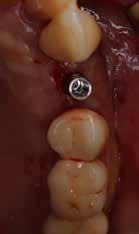

A behelyeztt implantátum primer stabilitását megfelelőnek ítéltük (kb. 40 Ncm) az azonnali terheléshez (9. kép).

Az extrakciót megelőző szituációs lenyomat alapján gyári, titán, ideiglenes abutment felhasználásával, a szék mellett készített, csavaros rögzítésű, azonnali akrilát ideiglenes koronával láttuk el, melyet 20 Ncm nyomatékkal rögzítettünk (10. kép). Az azonnali terhelés szabályainak megfelelően, az ideiglenes korona nem volt kontaktusban a szomszédos és az antagonista fogakkal.

6. kép: Implantátum-ágy preparáció. 7. a–b. képek: Implantátum behelyezés. 8. kép: A behelyezett implantátum. 10. a–b képek: Azonnali ideiglenes korona készítése. 9. kép: Megfelelő primer stabilitás.